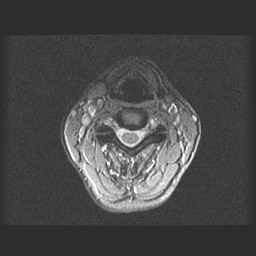

LWZ